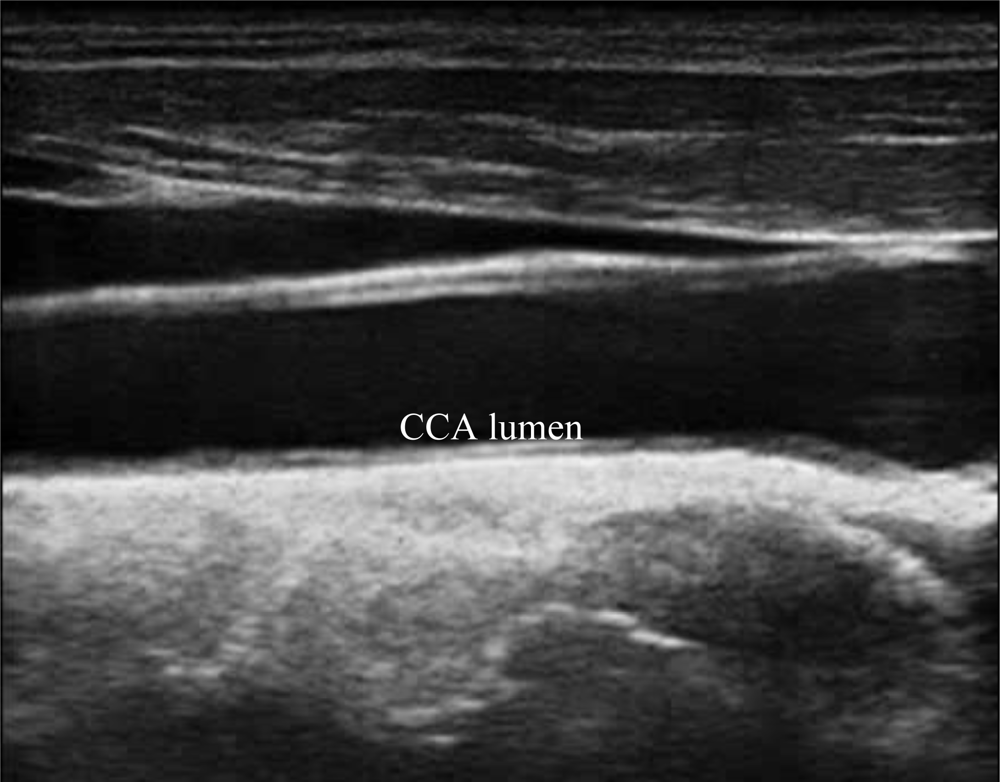

A typical B-mode image is shown in Figure 1. There are plaques on both near and far walls. On the contrary, a typical CCA image without plaque having thin and thick IMT is shown in Figures 2 and 3, respectively. Outlining the boundaries of intima and adventitia is not easy, especially on the near wall. Some features have been studied in previous studies [7,11], in which the most frequently used feature is the gradient of gray-values. From our previous studies [7,14,17], it is found that MacLeod operator combined with some specific enhancement filters are very suitable for feature extraction in intima and adventitia detections.

We have tested three image sequences: S1, S2, and S3, they include plaques, thin, and thick IMT, respectively. All sequences have at least three heart cycles. Figures 6 to 8 show the test results of IMT detection on the far wall, whereas Figures 9 to 11 show the test results of IMT detection on the near wall of the three sequences.

In Figure 6 there is a plaque on the right-hand side which is successfully detected. A total of 78 images are in sequence S1. Another example shows the ability to detect a thin IMT as shown in Figure 7. A total of 111 images are in sequence S2. Figure 8 shows the thick IMT test result. A total of 86 images are in sequence S3.